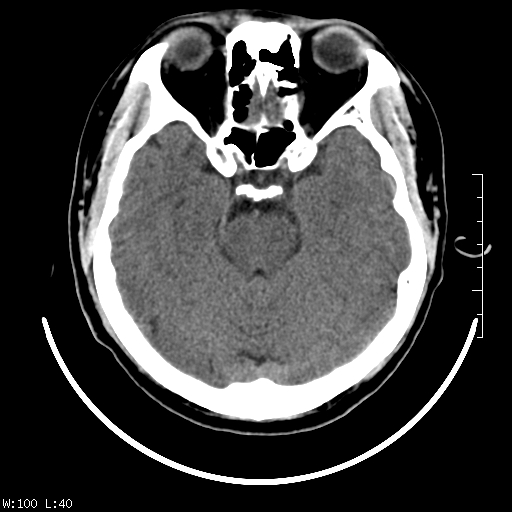

标题: CT22236:男,45,经常头痛。看看脑干正常吗? [打印本页]

标题: CT22236:男,45,经常头痛。看看脑干正常吗?

未见明显异常,建议ct增强或mri检查。

没见异常密度及形态改变啊,我认为是正常的。

颅脑ct轴位平扫颅内未见明确异常。

颅脑ct平扫未见明确异常,必要时mri检查。

颅脑ct平扫未见异常